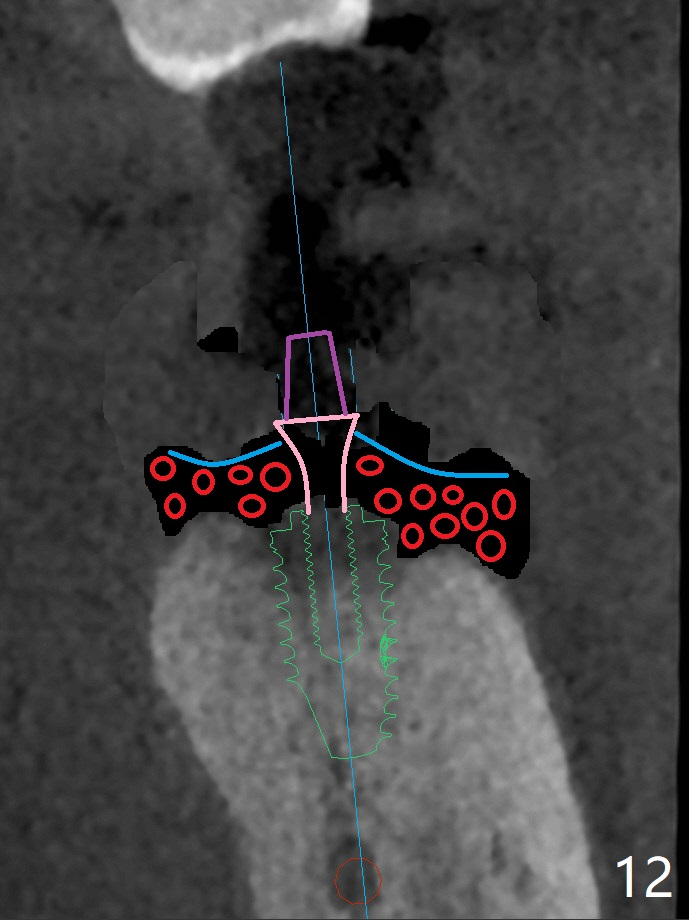

50岁男两年前不肯拔除左下7(图一),现在主动要求治疗(图二),需要做位点保留?怎么做的好?怎么收拾不动脑筋的惨剧(图三:仅远中牙槽窝植骨)?其实需要掀开近中粘骨膜(图四:箭头),然后植骨(红圆圈)。术后4.5个月近中缺损(图五:*),需要植牙植入很低(图六),离邻牙CEJ(<)很远。因此植体应该植入浅些(图七(CT矢状切面):箭头),离牙龈3毫米。放置袖3毫米(图八:粉红色)基台(紫色),然后在基台和植牙浅部植入粘性骨粉(图九:红圆圈)以及PRF膜(蓝线)。从冠状切面来看,颊侧(图十:B)需要多植骨,植牙前翻瓣(图十一:箭头),放置基台后(图十二),放置骨粉,膜,缝合。No Deviation 14 手术 Xin Wei, DDS, PhD, MS 1st edition 09/22/2020, last revision 03/02/2021